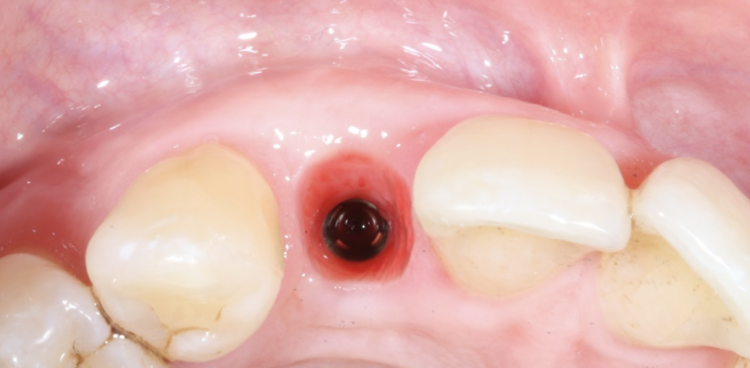

The second surgery involved a palatal crestal incision and a full thickness flap elevation revealing good turnover of bone graft into host bone. A bone level implant was placed in an appropriate three-dimensional position completely surrounded by new bone and no additional bone grafting was required. A 4mm healing cap was placed.

The provisional stages

Three months later a small crestal incision was performed to expose and remove the healing cap and impressions taken to construct an under-contoured screw-retained provisional crown. Over a period of two visits, composite was incrementally added to the subgingival portion of the temporary crown to expand and modify the soft tissue emergence profile until an acceptable shape was achieved.